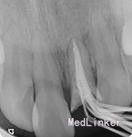

2.一次性根充后临时桩冠修复,观察两周。

感谢分享~资料图片比较完善,试尖片和根充片都有。目前临床多采用纤维树脂桩核修复,在充分考虑剩余牙体组织抗力的前提下,要尽可能扩大桩核的粘结面积